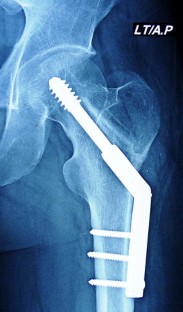

Dynamic hip screw and fibular strut graft for fixation of fresh femoral neck fracture with posterior comminution

Posterior comminution of the femoral neck fracture is a major cause of delayed and non-union owing to the loss of the buttressing effect against the posterior rotation. When a femoral neck fracture with posterior comminution is anatomically reduced, only the anterior portions of the femoral neck fracture surfaces are brought into contact leaving a posterior defect. The purpose of this study was to evaluate the use of fibular strut grafting and dynamic hip screw (DHS) for fresh femoral neck fractures with posterior comminution in young patient less than 50 years.

Between October 2012 and March 2016, 35 patients aged 20–50 years, 30 men and 5 women underwent fixation using DHS and fibular strut grafts for Garden grades III (25 patients) and IV (10 patients) femoral neck fractures with posterior comminution. All fractures were reduced by closed methods, and no hip was aspirated. Clinical and radiological outcomes were evaluated.

All patients were in the age group of 20–50 years (mean 37 years). The mean delay in presentation after injury was 1 day. The mean final follow-up for these 35 patients was 27.2 months. Healing of the femoral neck was attained in 34 cases, with an average time to union of 4.8 months (range 4–8 months). One patient underwent arthroplasty due to failure of fixation. According to the Harris hip score, outcome was good to excellent in 30 patients, fair in 4, and poor in 1.

In our study, only one patient developed non-union and no patients had avascular necrosis of the femoral head. Closed reduction, fibular strut grafts, and DHS fixation is a reliable procedure for femoral neck fractures with posterior comminution in young adults.

Fig. 2